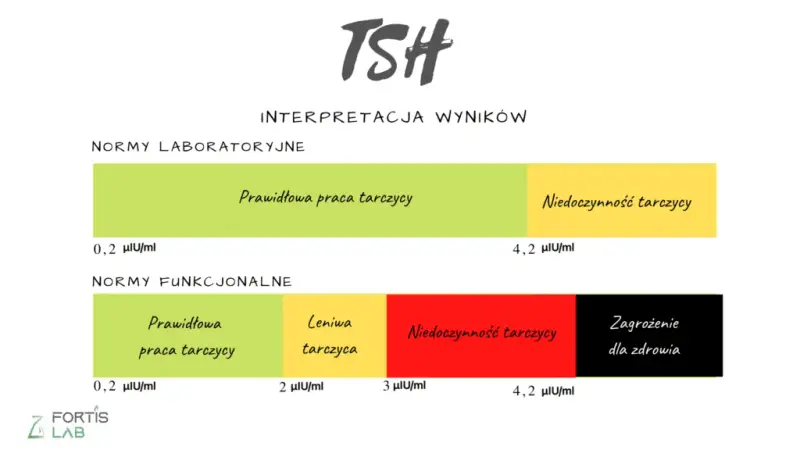

Dowiedz się, co to jest badanie TSH. Poznaj normy, objawy zaburzeń tarczycy i jak interpretować wyniki. Przeczytaj nasz kompleksowy przewodnik!